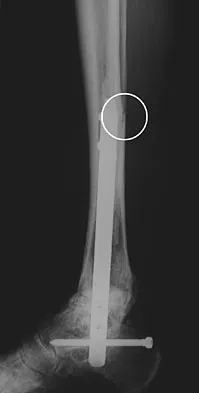

A patient with rheumatoid arthritis with both ankle and subtalar involvement was treated as shown in Figures 11a and 11b. What complication is unique to this type of fixation?

Explanation

The interlocking screws at the proximal end of the rod can act as a stress riser and lead to fracture. Postoperative pain at this level should prompt inclusion of this diagnosis in the differential. Removing the screws following bone union can decrease the chances of this occurring. A short rod that avoids the diaphyseal area may also be beneficial. Rotatory deformity is controlled by the perpendicularly oriented distal transfixion screws. Talar osteonecrosis would be unusual since the dissection can be minimized with an intramedullary rod. Any type of hardware can fail if the construct does not lead to a solid arthrodesis. Nunley JA, Pfeffer GB, Sanders RW, et al (eds): Advanced Reconstruction: Foot and Ankle. Rosemont, IL, American Academy of Orthopaedic Surgeons, 2004, pp 236-237. Thordarson DB, Chang D: Stress fractures and tibial cortical hypertrophy after tibiotalocalcaneal arthrodesis with an intramedullary nail. Foot Ankle Int 1999;20:497-500.